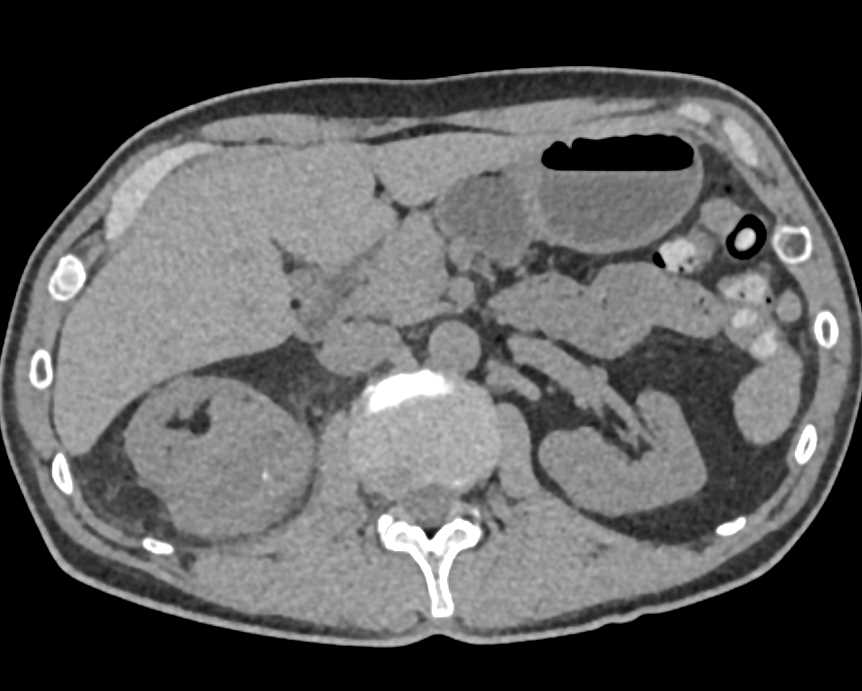

Renal Cell Carcinoma Upper Pole Right Kidney